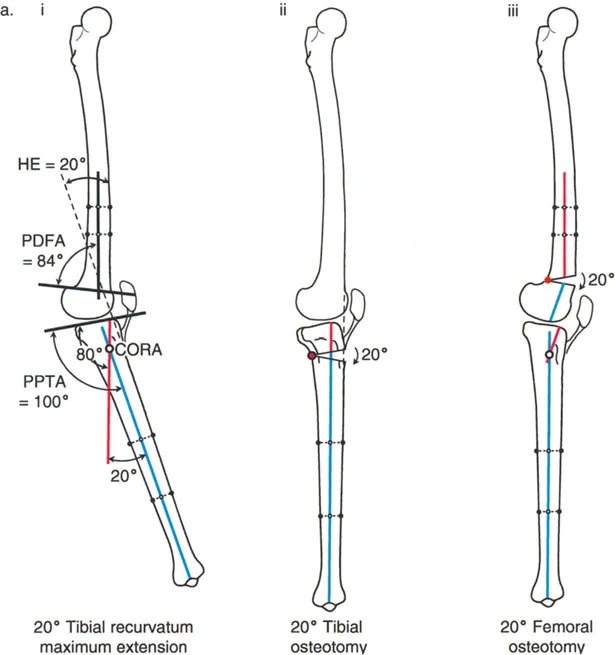

- تحدُّد حركة الركبة (Flexion Deformity - FFD): عدم القدرة على مد الركبة بالكامل، بحيث تظل الركبة في وضعية انثناء جزئي حتى عند محاولة فردها. يمكن أن يكون هذا ناتجًا عن تشوهات عظمية (مثل تقوس عظم الفخذ أو الساق للأمام) أو تقلصات في الأنسجة الرخوة (الأوتار والعضلات).

- الركبة الارتدادية (Recurvatum Deformity - Hyperextension): تمدد الركبة بشكل مفرط للخلف (فرط البسط)، أي تجاوز نقطة الاستقامة الطبيعية. يمكن أن يكون هذا ناتجًا عن ضعف العضلات (خاصة أوتار الركبة) أو تشوهات عظمية.

- الأشعة السينية الطويلة للطرف السفلي بالكامل أثناء الوقوف (Standing Long-Leg AP View): تُعد هذه الأشعة حاسمة لتقييم المحاذاة الميكانيكية للطرف السفلي بأكمله. تُظهر بدقة درجة الانحراف الأفحج (Varus) أو الأروح (Valgus) وتساعد في تحديد مركز دوران التشوه (CORA).

- الأشعة الجانبية الطويلة للطرف السفلي بالكامل أثناء الوقوف في أقصى بسط (Standing Long-Leg Lateral View in Maximum Extension): تُستخدم لتقييم تحدد حركة الركبة (FFD) والركبة الارتدادية (Recurvatum)، وتحديد ما إذا كان التشوه عظميًا أو ناتجًا عن تقلص في الأنسجة الرخوة.

تصحيح تحدد حركة الركبة (Flexion Deformity - FFD)

تحدُّد حركة الركبة هو عدم القدرة على مد الركبة بالكامل. يمكن أن يكون سببه عظميًا أو ناتجًا عن تقلص في الأنسجة الرخوة.

- التشخيص الدقيق: يجب تحديد ما إذا كان تحدد الحركة ناتجًا عن تشوه عظمي (تقوس أمامي في الفخذ أو الساق) أو تقلص في الأنسجة الرخوة (الأوتار الخلفية، محفظة المفصل).

- قطع العظم التمديدي (Extension Osteotomy):

- إذا كان التشوه عظميًا، يتم إجراء قطع عظم تمديدي في عظم الفخذ أو الساق لتصحيح التقوس.

- الأستاذ الدكتور محمد هطيف يؤكد على أهمية عدم تصحيح الساق بأكثر من 90 درجة PPTA لتجنب فقدان الميل الخلفي الطبيعي للساق.

تصحيح الركبة الارتدادية (Recurvatum Deformity - Hyperextension)

الركبة الارتدادية هي فرط البسط في الركبة. غالبًا ما تكون غير مصحوبة بأعراض في الأشخاص ذوي العضلات السليمة، ولكنها قد تسبب مشاكل في حالات ضعف العضلات أو التشوهات العظمية.

- التشخيص: يجب تحديد ما إذا كانت الارتدادية عظمية (تقوس خلفي في الفخذ أو الساق) أو ناتجة عن رخاوة في الأنسجة الرخوة أو ضعف عضلي.

- قطع العظم الانثنائي (Flexion Osteotomy):

- إذا كان التشوه عظميًا (تقوس خلفي)، يتم إجراء قطع عظم انثنائي في عظم الفخذ أو الساق لتصحيح الارتدادية.

- الأستاذ الدكتور محمد هطيف يشدد على أهمية عدم استخدام قطع عظم الفخذ الانثنائي لتصحيح ارتدادية الساق، والعكس صحيح، لتجنب الانزلاق الخلفي أو الأمامي للركبة.

- اعتبارات خاصة: في المرضى الذين يعانون من ضعف عضلي (مثل شلل الأطفال)، قد يحتاج التصحيح إلى فرط تصحيح بسيط (overcorrection) إلى وضعية انثناء لضمان ثبات الركبة ومنع فرط البسط غير المتحكم فيه.